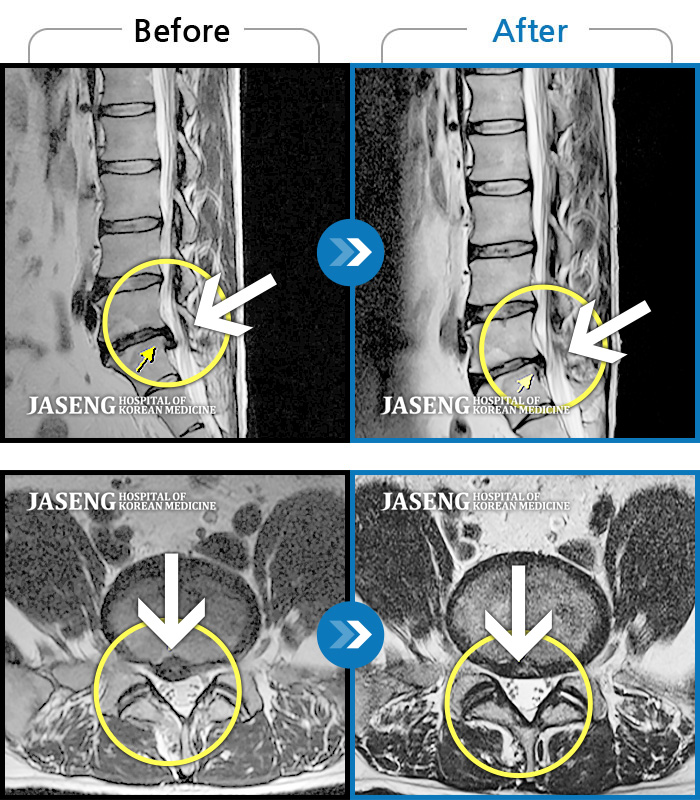

허리디스크

광주 · 장영우 원장

양측 허리부터 좌측 다리까지 이어지는 저림과 통증으로 걷기 힘들어 내원하였습니다.

촬영시기

2024.11.22 ~ 2025.05.16

2025.05.30